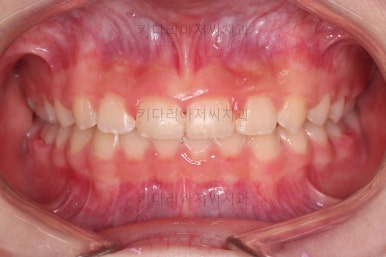

과개교합, 옥니, 앵글씨 2급 부정교합 모두 좋아지고 있어요.

마무리를 해줍니다.

앞니 각도가 매우 좋아졌고요.(옥니 개선) 위 아래 앞니가 덮는 정도도 개선되었어요.(과개교합, 딥바이트)

엉성했던 어금니 맞물림도 매우 좋아졌어요.(앵글씨 2급 부정교합)